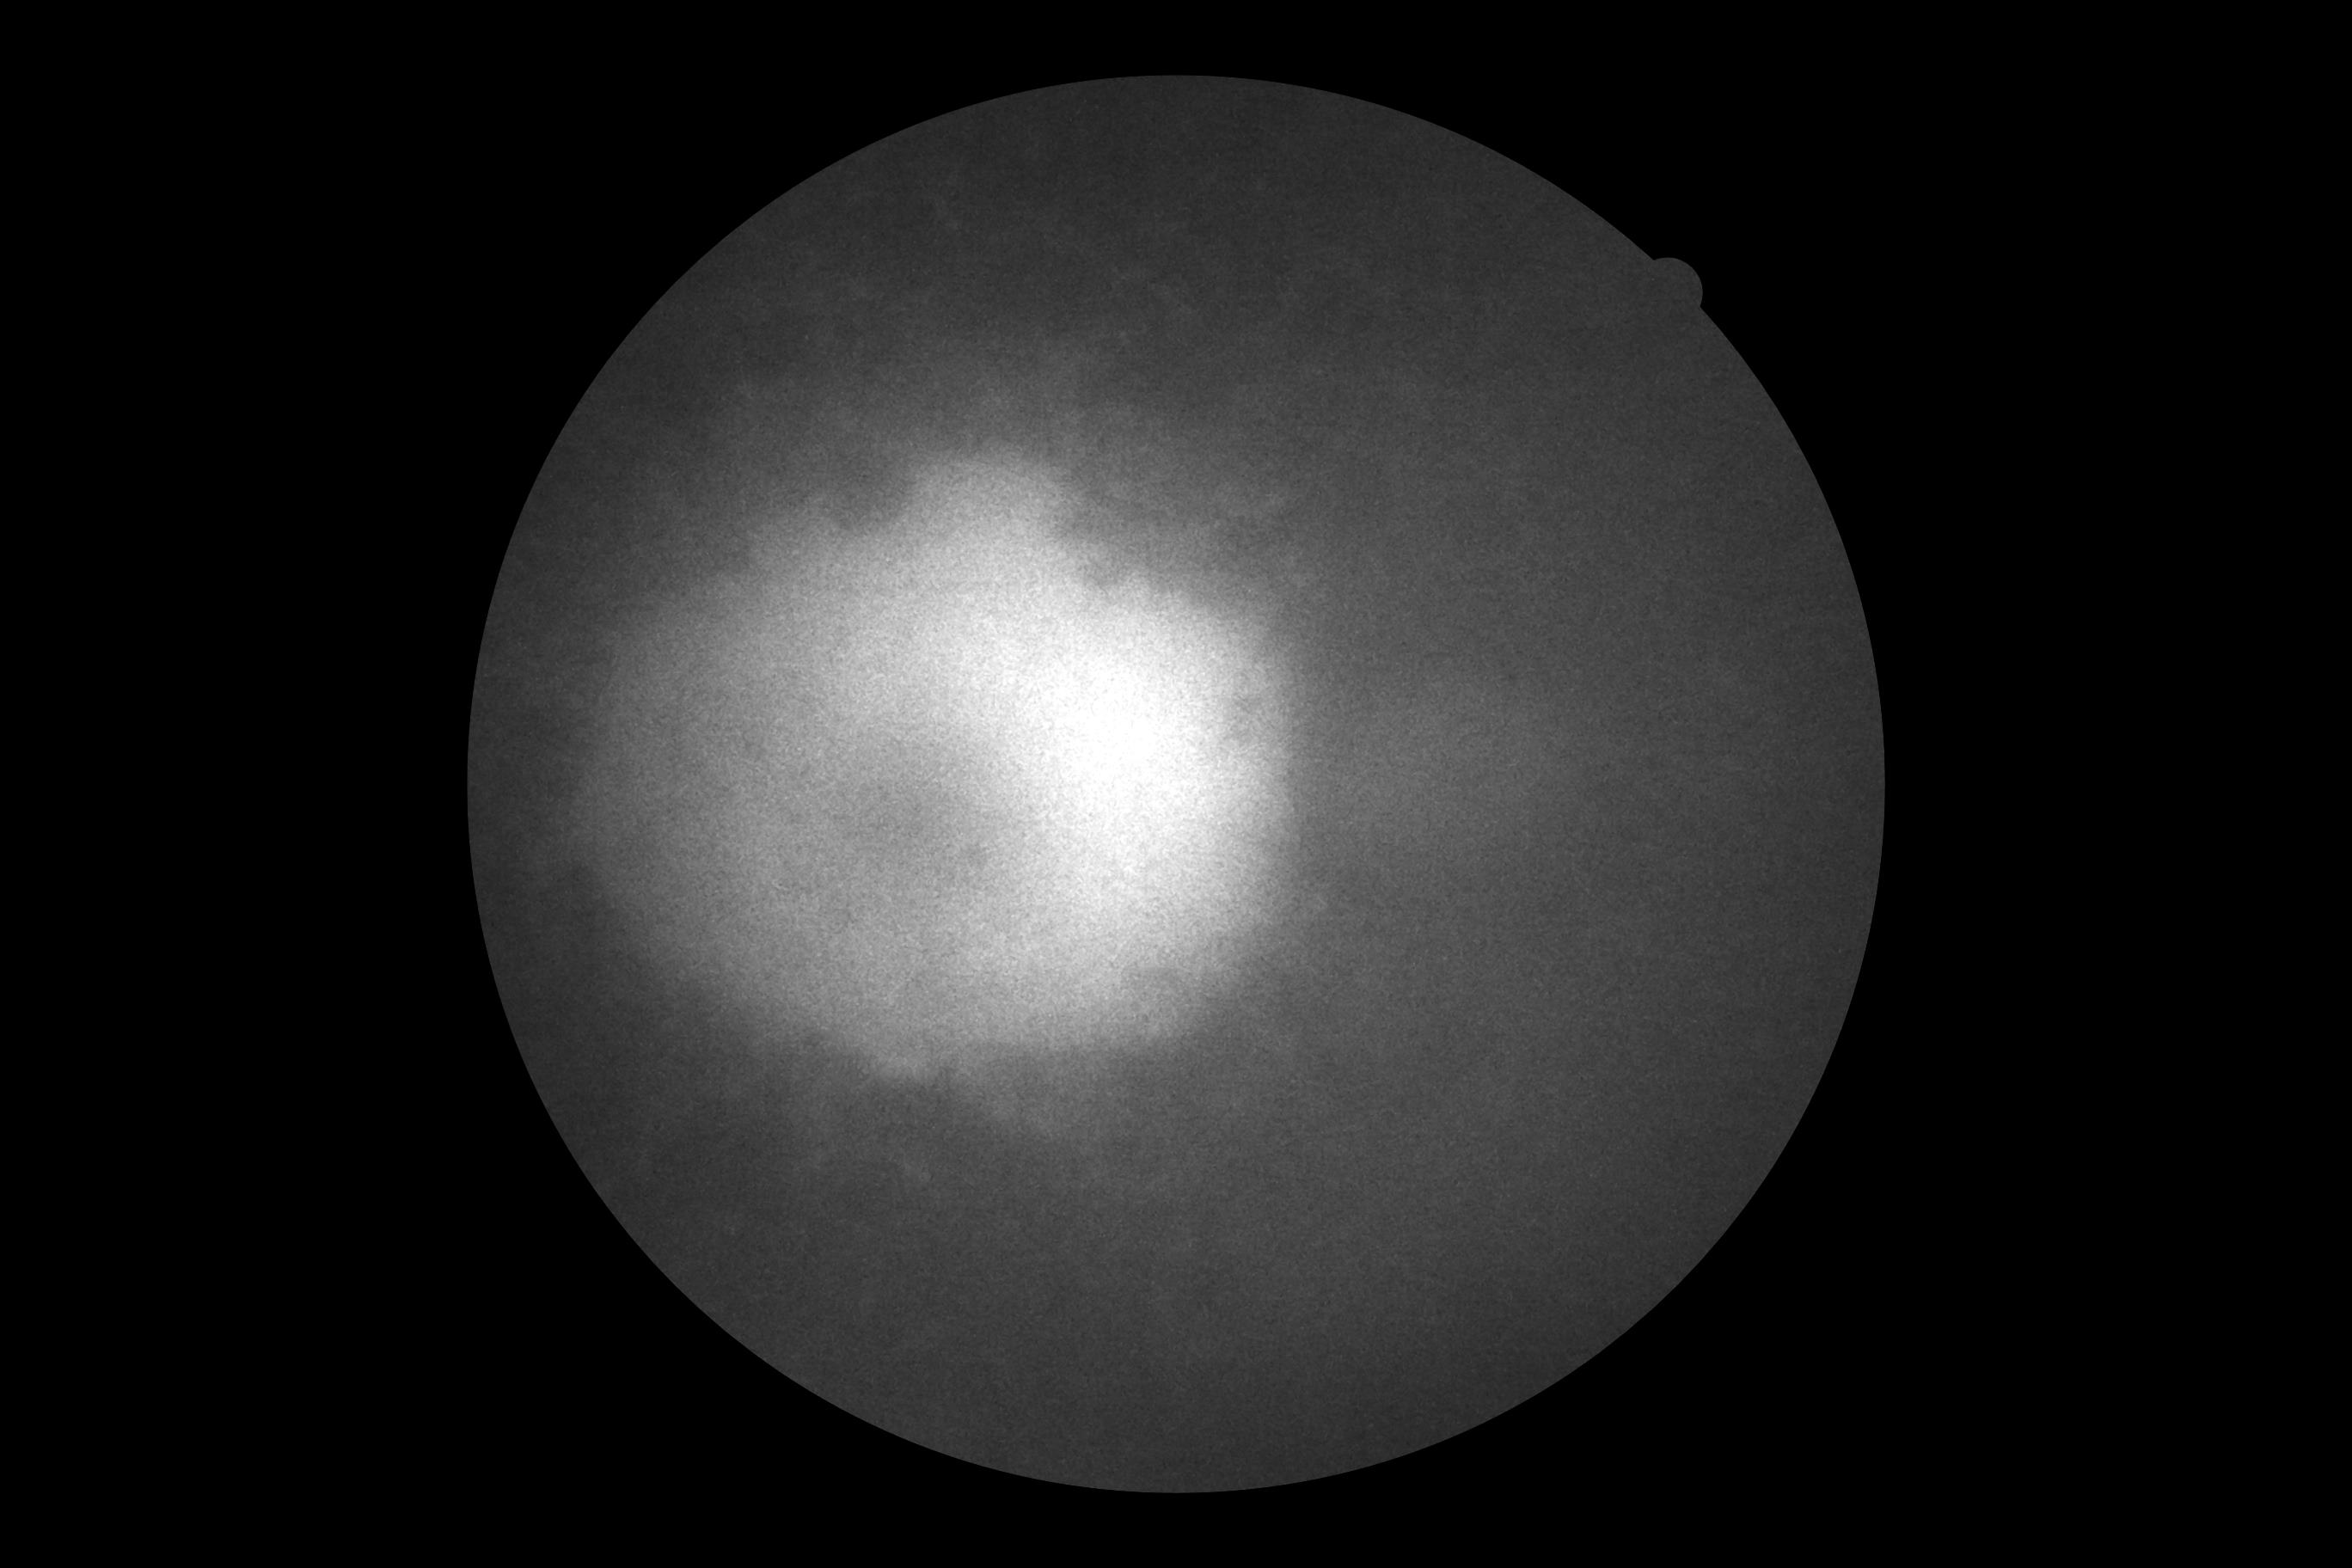

Пігментний ретиніт (пацієнт з артифакією) СЛО-зображення отримане за допомогою оптичного-когерентного томографа Canon Xephilio OCT A1

Пігментний ретиніт (пацієнт з артифакією) зображення отримане за допомогою оптичного-когерентного томографа Canon Xephilio OCT A1 (псевдоколір, High Definition)